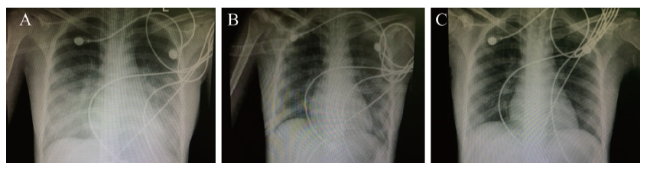

患者入我院后未再发热,入院后继续予甲泼尼龙口服24 mg/d、去甲肾上腺素升压、蛋白扩容、护肝、护胃、鼻导管吸氧等对症支持治疗。入院第3日08:00查血常规:血红蛋白 68 g/L,红细胞 2.75×1012/L,白细胞7.76×109/L,中性粒细胞0.735,血小板 159×109/L,予输注同型红细胞2 U,21:30患者开始出现咳嗽,经皮血氧饱和度(SpO2)逐渐下降至0.88,查动脉血气:pH 7.46,PaO2 47 mm Hg,PaCO2 34 mmHg,剩余碱 0.5 mmol/L,HCO3- 24.2 mmol/L,乳酸 8.1 mmol/L,予加用面罩吸氧后SpO2可维持在0.90以上。入院第4日02:08患者咳嗽加剧,咳出少量粉红色分泌物,伴有呼吸困难及胸闷不适,查氨基末端脑钠肽前体(NT-proBNP)7300 ng/L,动脉血气:pH 7.12,PaO2 39 mm Hg,PaCO2 72 mm Hg,剩余碱-6.3 mmol/L,HCO3- 23.4 mmol/L,乳酸 10.2 mmol/L。血常规:白细胞 12.85×109/L,中性粒细胞0.731,红细胞2.79×1012/L,血小板186×109/L,血红蛋白73 g/L。心电图较入院时未见明显变化,心梗3项未见异常。床旁X线胸片示双中下肺野有斑片状稍高密度影,边缘模糊,见图1A。考虑为急性左侧心力衰竭、ARDS及混合性失代偿期酸中毒,立即行床旁气管插管接呼吸机辅助通气及股静脉置管行床旁连续肾脏替代疗法(CRRT)、强心、抗心力衰竭、改善心肌代谢、营养心肌、镇静镇痛等治疗。入院第4日上午实验室检查结果回报抗心磷脂抗体 15.9 RU/ml。T-SPOT:A抗原 23个,B抗原14个。风湿2项、抗可溶性抗原(ENA)谱、SLE 3项、血管炎4项、抗磷脂抗体综合征3项、PPD试验、肥达+外-斐试验、全血找疟原虫、肝吸虫计数、粪便找阿米巴滋养体及疟原虫、EB病毒(EBV)+巨细胞病毒(CMV)DNA测定、G6PD +地中海贫血、溶血性贫血、维生素B12及叶酸测定、3点血浆皮质醇测定均未见异常。床旁双侧颈部、腋窝及腹股沟淋巴结彩超未见异常血供及肿瘤倾向。骨髓细胞学形态:增生性贫血伴反应性组织细胞增多骨髓象 [G/E = 3.85/1,铁染色外铁(+)]。骨髓活检:符合增生活跃骨髓象,见图2。考虑为AOSD合并休克、心力衰竭、ARD、中-重度贫血、混合性失代偿期酸中毒;予甲泼尼龙160 mg/d,连用3 d。入院第7日激素开始减量至100 mg,复查血常规:血红蛋白77 g/L,红细胞 2.04×1012/L,白细胞 12.01×109/L,中性粒细胞 0.808,血小板 131×109/L。床旁X线胸片:双中下肺野斑片状稍高密度影较前吸收,见图1B,考虑患者存在肺部感染,予抗感染(卡泊芬净+美罗培南)治疗。入院后第9日患者血压、血氧稳定、乳酸降至正常范围、肝功能恢复正常、肺部渗出基本吸收,见图1C,停用去甲肾上腺素、护肝药、床边CRRT及呼吸机治疗,并改用头孢哌酮钠舒巴坦钠抗感染治疗。入院后第10日,甲泼尼龙剂量减至80 mg/d,并加用吗替麦考酚酯0.5 g每日2次治疗。入院后第11日复查血常规白细胞及中性粒百分比恢复至正常范围,甲泼尼龙减量至60 mg/d,吗替麦考酚酯剂量增至0.75 g每日2次,加用羟氯喹200 mg每日2次治疗,降级用头孢硫脒抗感染,入院后第16日查正电子发射断层显像/计算机断层显像(PET/CT):全身未见实质性恶性肿瘤影响改变;脾大,氟代脱氧葡萄糖(FDG)代谢弥漫性轻度增高,提示脾功能亢进;全身骨髓FDG代谢弥漫性轻度增高;甲状腺左侧叶结节影,代谢未见增高,考虑为良性病变,腺瘤待排;双侧蝶窦、筛窦及上颌窦炎症。心脏彩超示心包微量积液,其余未见异常。提示肿大的淋巴结及肝脏经治疗后恢复正常、心功能恢复正常,表明治疗有效果,甲泼尼龙继续减量至40 mg/d,维持1周未见病情复发,期间多次查血常规,白细胞及中性粒细胞、血小板均正常,血红蛋白逐渐升高至105 g/L,血清铁蛋白降至343 μg/L。入院后第24日,患者改口服甲泼尼龙32 mg/d,带药出院治疗,随后定期在我院门诊随访,激素继续缓慢减量至口服8 mg/d甲泼尼龙及改善病情抗风湿药(DMARD)维持治疗。随访1年余,患者病情未再复发,监测血常规、肝功能及血清铁蛋白均正常。

图1 一例重症AOSD患者的肺部病灶变化

A:入院第4日床旁X线胸片示双中下肺野见斑片状稍高密度影,边缘模糊;B:入院第7日床旁X线胸片示双中下肺野斑片状稍高密度影较前吸收;C:入院第9日床旁X线胸片示肺部渗出基本吸收